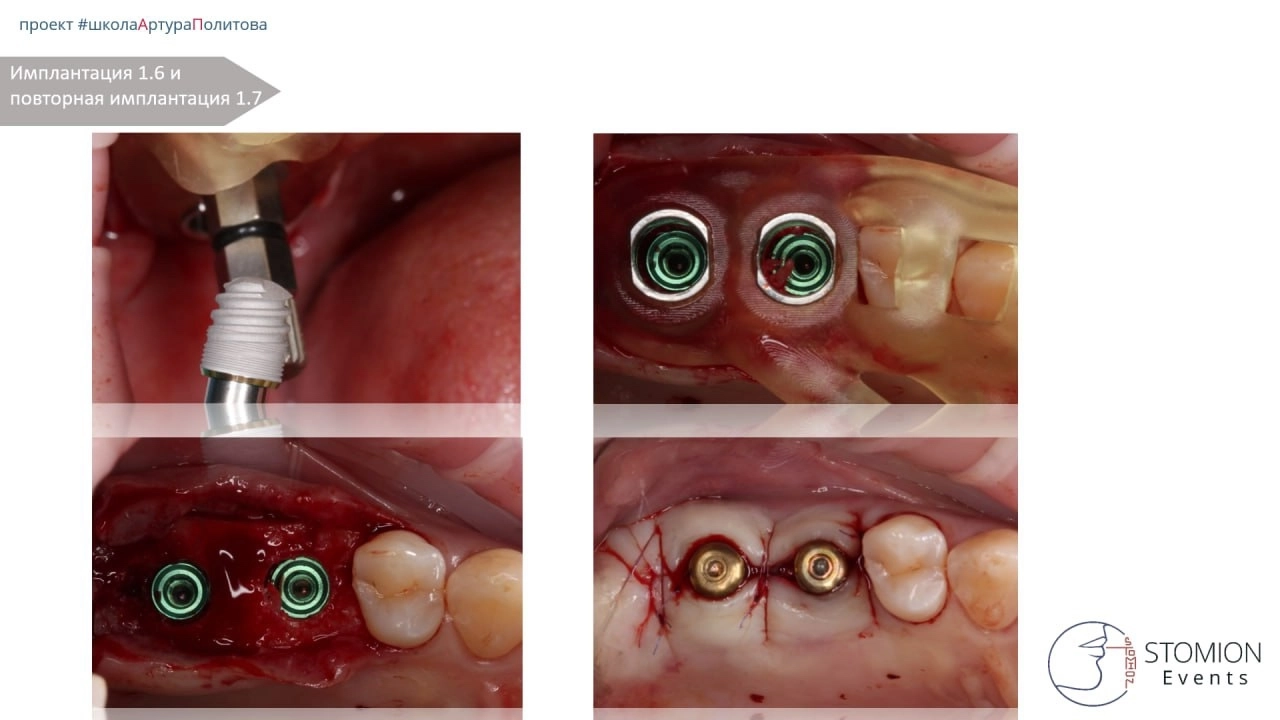

План лечения (этап 2)

— Через 3 месяца проведена имплантация в области 1.6 и 1.7.

— Установлена временная конструкция с уровня мультиюнита.

Однако через 3 месяца выявлено отсутствие остеоинтеграции имплантата в позиции 1.7. Проведено удаление и повторная установка по тому же шаблону.